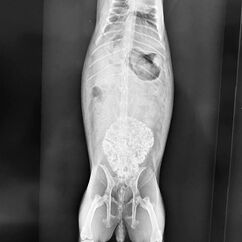

Zu jeder Impfung gehört eine Allgemeinuntersuchung. Mit 6 Jahren gehört Lotti zu den älteren Kaninchen und gerade bei Weibchen kommen dann Gebärmutterprobleme häufig vor. Bei der Allgemeinuntersuchung fiel mir dann eine etwa faustgroß derbe Umfangsvermehrung auf (so heißt medizinisch erst einmal alles, was nicht da sein sollte). Wir haben geröngt und Blut genommen, nicht, dass da noch eine Überraschung zu Tage tritt und haben schon im Röntgen gesehen, dass da etwas ganz und gar nicht stimmt. Lotti hatte eine kalzifizierte Umfangsvermehrung im Bauch. Das kann jetzt einiges sein, daher hat ein sehr netter Kollege einmal mit dem Ultraschall genauer nachgeschaut und der Verdacht eines Gebärmuttertumors war dann sehr stark. Im Blutbild zeigte sich eine heftige Entzündung, was nicht so ganz zu einem Tumor passt. Lotti wurde mit Schmerzmitteln und einem Antibiotikum abgedeckt und innerhalb einer Woche wurde sie auch zunehmend schmerzhaft, das zeigt sie trotz Schmerzmitteln deutlich. Die Kastration ging einfach und besser, als wir dachten, aber sie war deutlich schwieriger, als eine normale Kastration, denn Tumore haben eine ganz unangenehme Eigenart : Sie werden mit Blut versorgt und es sind meist sehr dicke Blutgefäße. Der Tumor ist 6x4x5cm groß und wiegt knapp 100g (viel bei gerade 1.8kg Gesamtgewicht). Zum Glück dürfen wir den Tumor auch einschicken, es steht einiges im Raum und wir wollen schon wissen, wie es prognostisch aussieht. Das Ergebnis zeigt einen bösartigen Tumor, wie es leider bei den Weibchen häufig vor kommt. Die Ränder sind sauber, an einer Stelle war er leider offen, das haben wir in der OP bereits gesehen.